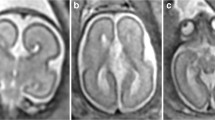

The anatomy of the CSPV is understood by appreciating its relationship with the corpus callosum and fornices and there was remarkable consistency between the anatomy of those structures shown on atlases of post-mortem sections and on the iuMR imaging from normal foetuses reported here (Figs. 4, 5 and 6). As expected, the corpus callosum appeared fully formed on iuMR imaging in all 200 cases between 18 and 37 gestational weeks (gw), inasmuch as its full cranio-caudal extent had been achieved and its three major anatomical subdivisions (genu, body and splenium) could all be recognised routinely. The inferior border of the corpus callosum indicates the superior extent of the CSPV. Inferiorly, the origin of the fornices from the fimbriae (the major efferent pathway of the hippocampus) can be seen, although there is insufficient spatial and contrast resolution to separate the fimbria from the rest of the mesial temporal lobe on iuMR imaging. As such, the posterior part of the fornices (crura) can be seen exiting from the posterior part of the mesial temporal lobe and pass towards the splenium of the corpus callosum. This feature can be demonstrated on iuMR imaging in the majority of foetuses studied (Figs. 4 and 5), particularly on the thinner partitions available from volume data sets reconstructed in the coronal plane. The crura of the fornices come into close proximity with its contra-lateral partner in the vicinity of the splenium of the corpus callosum and it is not possible to differentiate the fornices from the splenium of the corpus callosum in this location. The fornices then arc forwards, away from the splenium, and diverge from the body of the corpus callosum but the septa of the CSPV extend between the corpus callosum and fornices. This is best appreciated in the coronal plane (Fig. 5) although the more cranial regions are well seen on sagittal images (Fig. 6). The septa of the CSPV are generally widely separated throughout but inferiorly they come into close proximity where they contact fused bodies of the fornices (Fig. 5).

Axial post-mortem specimens (a, c, e, g—with anatomical annotation modified from reference [9]) with equivalent axial reconstructions from T2W volume acquisitions (b, d, f, g) from 29 gw foetuses running from superior to inferior. Images in this plane show the crura of the fornices originating from the hippocampus and heading towards the splenium of the corpus callosum (arrowed on b and d) with the leaflets of the CSPV anteriorly (arrowheads on b). The fornices course anteriorly and are in close proximity (arrowed on f) before dividing around the anterior commissure (arrowheads on h)

Coronal post-mortem specimens (a, c, e, g—with anatomical annotation modified from reference [9]) and equivalent coronal T2W single-shot fast spin echo images (b, d, e, f) from 29 gw foetuses running from caudal to cranial. Images in this plane show the crura of the fornices originating from the fimbria of the hippocampi (arrowed on b) and heading towards the splenium of the corpus callosum (arrowed on d) and the relationship between the leaflets of the CSPV and body of the fornices inferiorly (arrowed on f). The fornix enters the brain parenchyma in the vicinity of the anterior commissure so the cranial images only show the leaflets of the CSPV (arrowed on h)

Midline sagittal post-mortem specimen (a—with anatomical annotation modified from reference [9]) and midline sagittal T2W single-shot fast spin echo image (b) from 29 gw foetuses. Images in this plane show the relationship between the corpus callosum and fornices (body of the fornices arrowed on b) therefore defining the fluid-filled central portion of the CSPV. Note the CSPV appears larger on the iuMR imaging, presumably because of loss of fluid pressure post-mortem